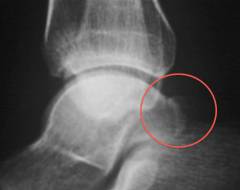

Рентгенография. На рентгеновском снимке видны трещины кости, переломы, смещение лодыжки. Но для оценки состояния мягких околосуставных тканей рентген неинформативен.

Признаки разрыва связок на рентгене:

- несоответствие суставных концов костей, их смещение вследствие разрыва связки;

- увеличение щели между таранной костью и берцовыми костями голени;

- увеличение объема мягких тканей.

Рентген делают в двух проекциях, это позволяет определить угол между костями голени и таранной костью. Если есть необходимость, то делают снимок с нагрузкой. Для этого, после обезболивания, стопе предают такое положение, чтобы напрячь исследуемые связки.

Рентгенография – основной метод диагностики переломов голеностопного сустава. Рентген делают в двух проекциях в передней и боковой. Это необходимо, чтобы не пропустить перелом.

Признаки перелома голеностопа на рентгене:

- линия перелома на наружной, внутренней лодыжке или таранной кости. Линия может проходить горизонтально, вертикально или винтообразно;

- нарушение контура кости в месте перелома;

- смещение суставных концов кости вследствие перелома и разрыва связок;

- смещение осколков кости. Между фрагментами кости видны клиновидные щели;

- признаки вывиха стопы – смещение таранной кости по отношению к костям голени.